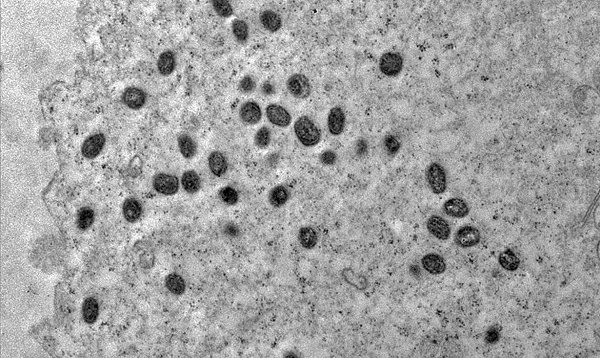

A Secretaria de Estado da Saúde Pública (Sesap) confirmou, nesta quinta-feira (23), três novos casos de Mpox no Rio Grande do Norte, registrados dentro da semana epidemiológica iniciada no dia 17. Os casos são considerados leves e os pacientes seguem em isolamento domiciliar, sob monitoramento das equipes de saúde.

Do total, dois casos foram identificados em Natal e um em São Gonçalo do Amarante, Região Metropolitana. Segundo a Sesap, todos recebem acompanhamento seguindo os protocolos estabelecidos para a doença.

Imagem: Reprodução